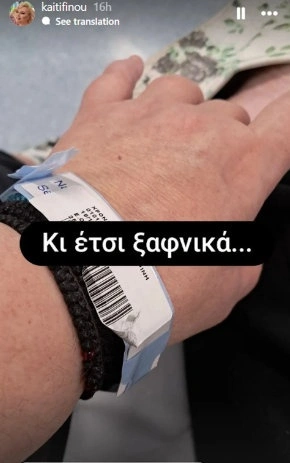

Στο νοσοκομείο νοσηλεύεται η Καίτη Φίνου η οποία ανέβασε και την πρώτη φωτογραφία από το κρεβάτι του πόνου.

Όπως αποκάλυψε η ηθοποιός, βρίσκεται στο νοσοκομείο από χθες και μάλιστα, όπως επεσήμανε, εμφανίστηκε ξαφνικά πρόβλημα υγείας το οποίο και την οδήγησε μέχρι εκεί.

Η Καίτη Φίνου, δεν αποκάλυψε τι ακριβώς τής συνέβη, όμως όπως έγραψε, από χθες δεν έχει φάει και δεν έχει πιεί τίποτα. Φαίνεται όμως πως πηγαίνει καλύτερα αφού σήμερα της έφεραν να φάει και να πιει νερό που τόσο λαχταρούσε.

Συγκεκριμένα έγραψε στην ανάρτησή της:

«Ούτε παραγγελία να το είχα κάνει. Φαγητό νοσοκομείο τέλειο έτσι; Δες τι φτιάχνουν εδώ! Επιτέλους θα φάω. Από χθες που έφτασα εδώ πέρα ούτε νερό δεν με αφήνουν να πιώ. Άντε καλή μας όρεξη και καλή Κυριακή παιδιά. Να προσέχετε. Επιτέλους φαΐ μετά από 24 ώρες. Ααα και νερό. Είχα κορακιάσει. Καλό Σαββατόβραδο».